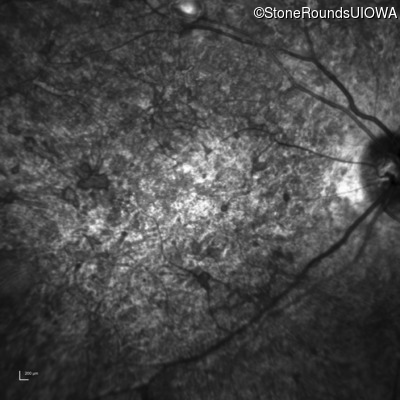

Infrared Fundus Photograph - Left - 20/400 sc

Exemplar